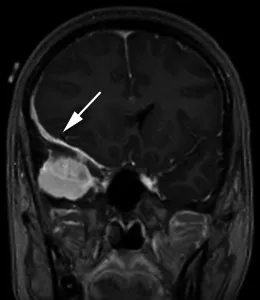

一名35岁头痛女性的造影后冠状T1加权序列显示,右中颅窝内有均匀增强的轴外质量,并有宽阔的硬脑膜尾(箭头)沿着蝶骨翼延伸,并围绕右额叶的侧面。肿块导致大脑镰下向左突出7毫米,右侧脑室消失。手术时的组织学结果为脑膜瘤(1级)